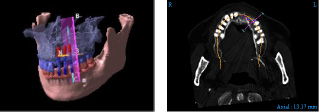

当医院では、CT検査をお勧めしております。

(CT撮影は提携している病院でおこないます。)

撮影したCTをインプラント専用ソフトで解析して、顎骨の状態をより詳しく調べることにより、最適なインプラント位置を診断し、精度の高い、安心・安全な手術を受けることが可能です。